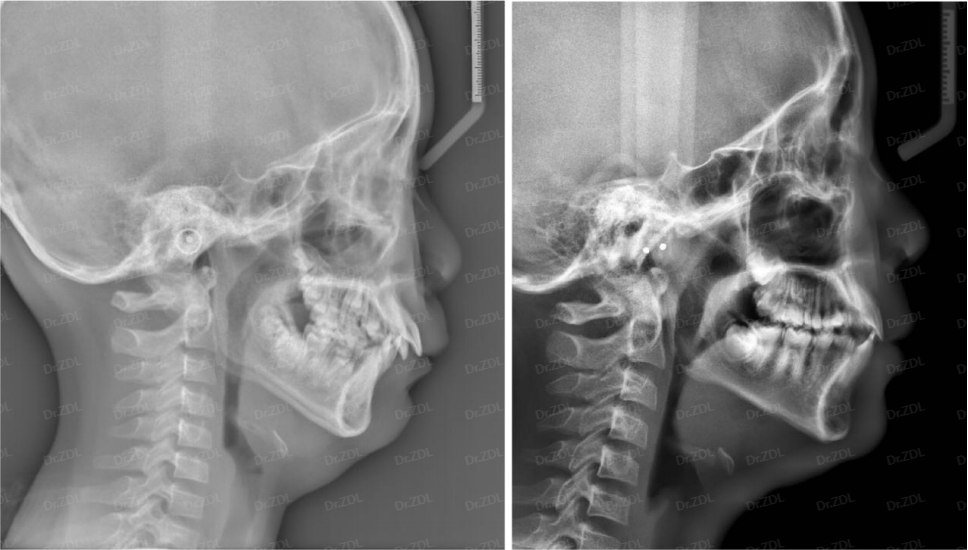

这位小朋友,主诉牙凸、牙不齐、没下巴,临床检查看上前牙III度深覆合深覆盖,骨性II类倾向,上颌牙弓狭窄,鼻唇角偏大、颏唇沟比较深。

根据孩子牙齿情况,采用Grace轨道式硅胶矫治器,恢复上下颌正常牙弓宽度,匹配上下颌牙弓形态,引导上下恒牙正常萌出,引导下颌前伸,并日常辅助唇肌功能训练。

佩戴 Grace10 个月,上下颌牙齿排齐良好,咬合打开良好,深覆合深覆盖得到改善,侧貌形态良好。

佩戴 Grace24 个月,上颌内收,下颌前伸,上下颌乳牙完全替换完成,牙弓形态正常,牙齿排齐良好,前牙正常覆合覆盖。